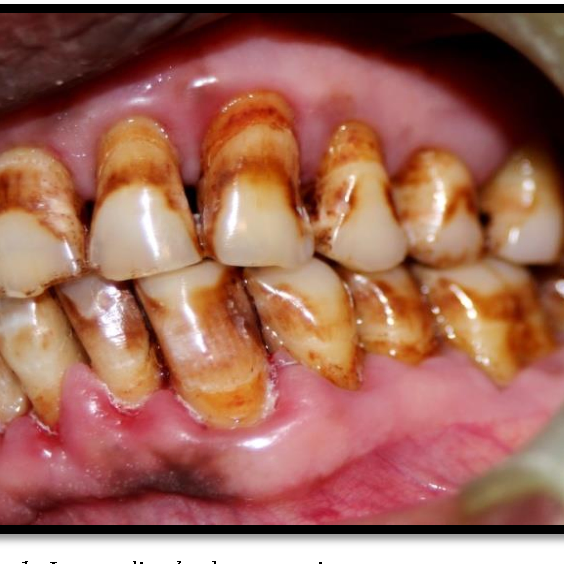

Causes of teeth stains

- Smoking and chewing tobacco not only increases your chances of gum disease, it can also cause your teeth to turn yellow.

- Diet, bright and dark-colored foods such as wine, coffee, tea, as well as certain fruits and vegetables (e.g. beets, tomatoes, blueberries, raspberries) can stain teeth.

- Poor oral hygiene, failing to brush and floss on the daily basis or not brushing thoroughly enough is a major contributor to tooth discoloration.

Teeth stains occur on the surface of the tooth or below the tooth enamel and some people develop both types of teeth stains.

Extrinsic Teeth Stains:

An extrinsic tooth stain is staining on the surface of the tooth. It occurs when stain particles, such as pigmented residue from food or drink, build-up in the film of protein that covers the tooth enamel